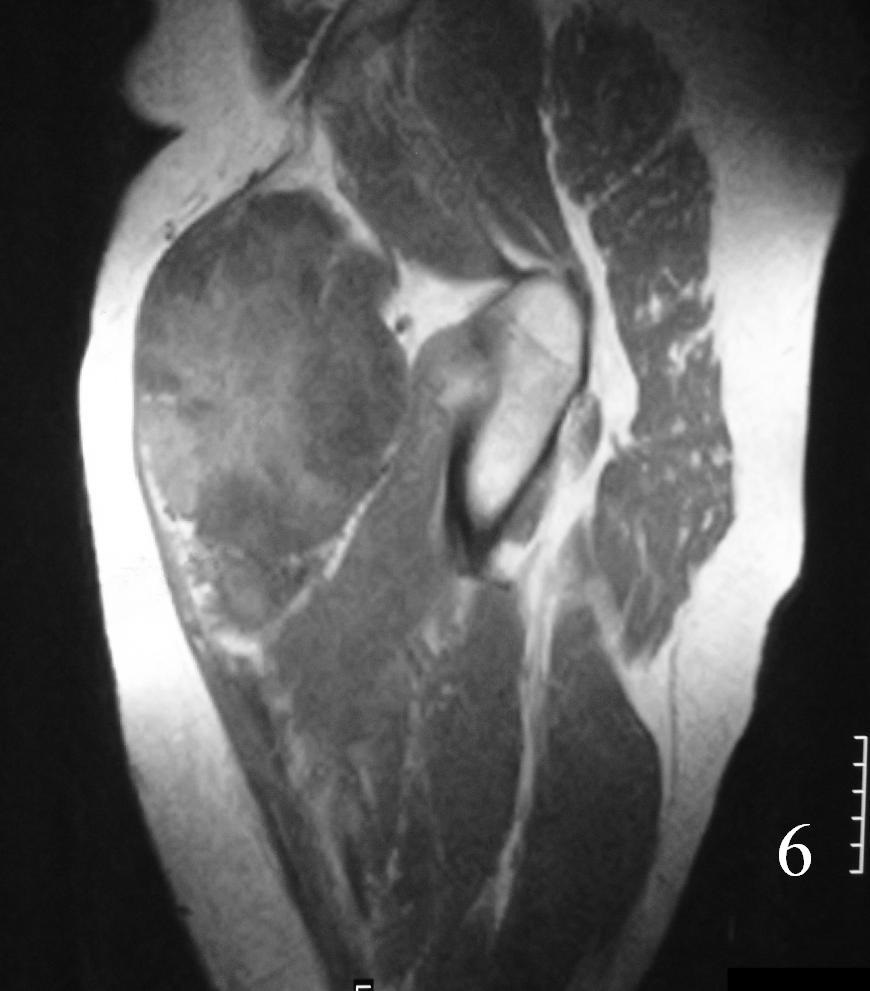

MRI (Fig. 3-7)

• Shows lobulated soft tissue mass

• Signal intensity similar to that of skeletal muscle on T1W

• Heterogenous signal intensity greater than that of fat on T2W

Fig. 6

Fig. 7

Fig. 3-7 Axial MRI of the lower extremity shows an extraskeletal soft tissue chondrosarcoma in different sequences with and without contrast (Fig. 3, 4, 5). Sagittal MRI (Fig. 6, 7) T1 with-without contrast demonstrates enhancement of the mass